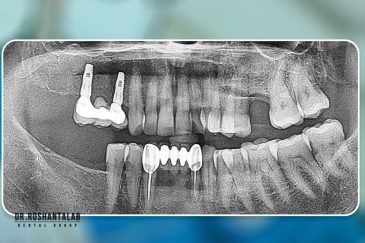

کلینیک تخصصی دکتر حسن روشن طلب با همکاری جمعی از متخصص ایمپلنت دندان و جراح فک و صورت بنام در حال فعالیت می باشد. این مجموعه مأموریت خود را ارائه خدمات تکمیلی دندانپزشکی در زمینه درمان های تخصصی و عمومی به شرح ذیل انجام می شود.

بهره مندی از دانش علمی و تجربه بالای موسس و جراحان این کلینیک، همچنین امکانات و تجهیزات به روز و کارآمد از جمله ویژگی های منحصر به فرد این کلینیک است. همچنین با ارائه خدمات درمانی با کیفیت و هزینه مناسب دندانپزشکی در رشت، تهران، اصفهان و استانبول ترکیه توانسته است در این سال ها لبخند رضایت بر صورت مراجعه کنندگان عزیزمان بگذارد.